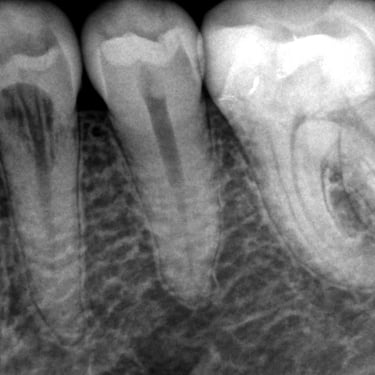

Reabsorción Interna

La reabsorción interna es la destrucción progresiva de la dentina desde el interior del diente hacia afuera, generalmente debido a un trauma o inflamación pulpar.

Los pacientes pueden notar un cambio de color en el diente.

Es necesario un tratamiento de conducto para detener el proceso y salvar el diente. Sin tratamiento, el diente puede debilitarse y fracturarse.